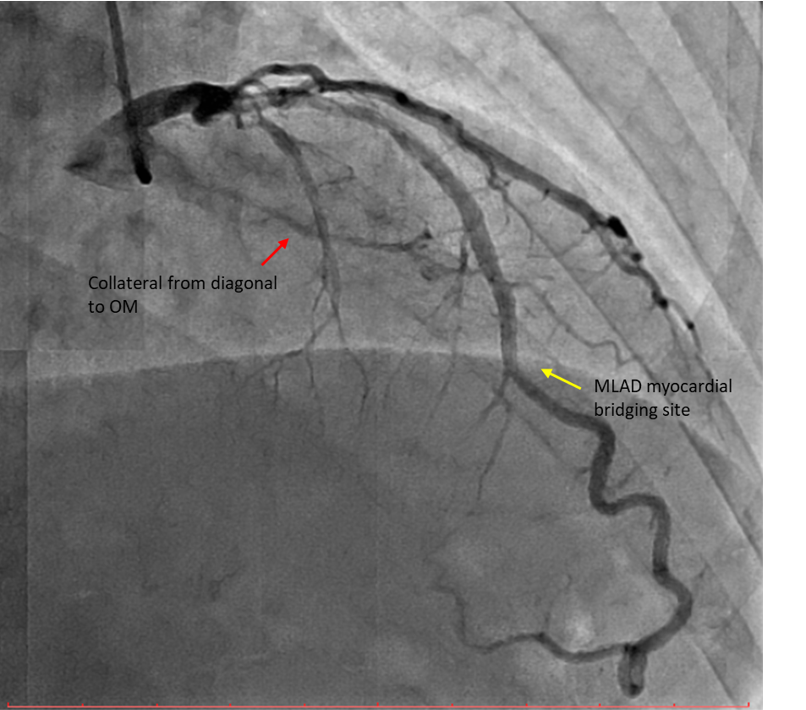

Diagnostic CAG:Left main stem: normalLeft anterior descending artery: proximal 30% stenosis, mid myocardial bridging, diagonal branch giving collateral to OM branchLeft circumflex artery: stent in distal LCX with ISR type IV 100% occlusionRight coronary artery: Dominant, mid 40-50% stenosis, PLV branch giving collateral to OM branch

Percutaneous coronary intervention (PCI) was performed via transradial approach with 6 Fr radial sheath. Left coronary system was engaged using EBU 3.0 6 Fr guiding catheter. We decided for antegrade approach. Initial attempt with Fielder XT-A wire with a microcatheter support failed to cross the in-stent restenosis (ISR) lesion. We escalated to Asahi Gaia Second wire and successfully crossed the lesion to OM branch. Subsequently, wire was exchanged to a workhorse wire Runthrough Floppy via microcatheter. Lesion site was first predilated with a semi-compliant balloon Pantera Pro 2.0x 15 mm. Then, IVUS was passed down which showed previous stent site undersized, vessel size distal LCX of 4.0 mm. We further predilated lesion site with scoring balloon Scoreflex Trio 3.5x15 mm, up to 22 atm. Lesion site was acceptably prepared, then Paclitaxel drug-coated balloon Prevail 4.0x25 mm was deployed at nominal 6 atm for 60 seconds. Repeated IVUS run showed good stent apposition with MSA of 9.5mm2 proximally and 6.6mm2 distally. Final fluoroscopic shot showed good result with TIMI 3 flow, no stent edge dissection. Patient was symptom-free after procedure and discharged the following day.